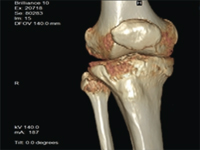

Zastosowanie ortobiologii w leczeniu ubytku kostnego na podstawie przedstawionego przypadku

Platelet Rich Plasma application in a bone loss case

SurgeryPlatelet rich plasma (PRP - Platelet Rich Plasma) is a concentrated volume of platelets dispersed in a small volume of plasma containing platelet-rich growth factors, used based on the based on the concept of orthobiologics. The strategy for using PRP is to use the patient's own blood as a a means of stimulating the regenerative processes of both soft tissue and bone tissue